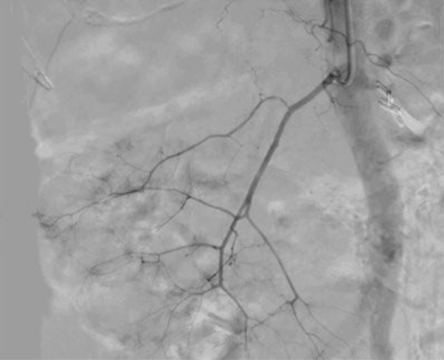

Через правую лучевую артерию последовательно селективно катетеризированы правая и левая почечные артерии. Выполнена ангиография, при которой визуализированы растянутые и деформированные сегментарные почечные артерии с периферическими ветвями, окружающими кисты, что является характерным рентгенологическим признаком наследственной поликистозной болезни почек.

Почечная артерия, заполненная контрастным веществом, до введения микроэмболов. |